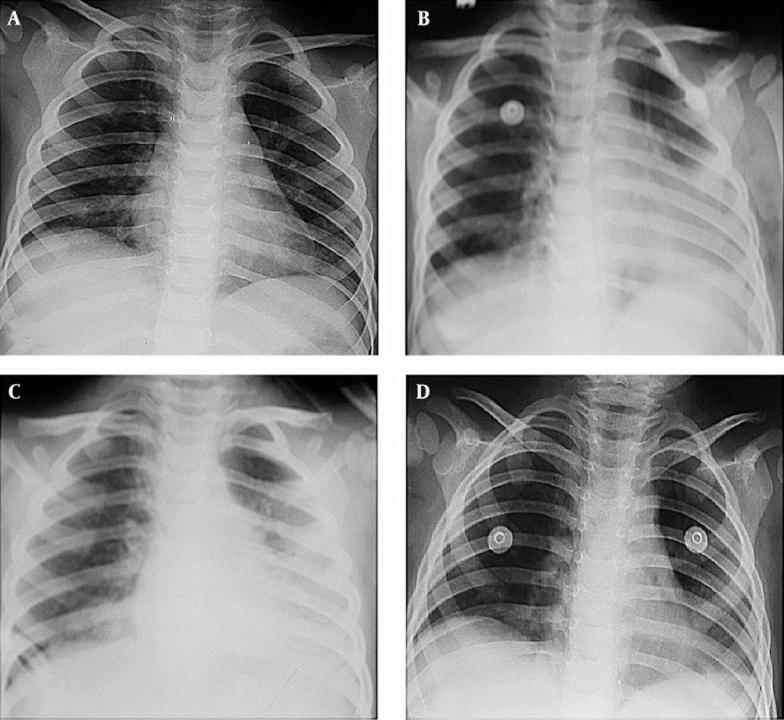

Of the six patients, 83.3% (n = 5) were male and 16.7% (n = 1) were female, with a mean age of 2.1 ± 0.49 years. The most common clinical signs were dyspnea (83.3%), fever (66.6%), and vomiting (66.6%). Owing to supportive treatments and the combined steroid treatment, respiratory distress diminished and there was no need for oxygen in any of the patients after 5 days. All patients were discharged without any sequelae.

The use of steroids in treating hydrocarbon pneumonias is still controversial. However, we suggest that the combined use of inhaled and intravenous steroids had positive effects on the clinical and radiological recovery of our patients.